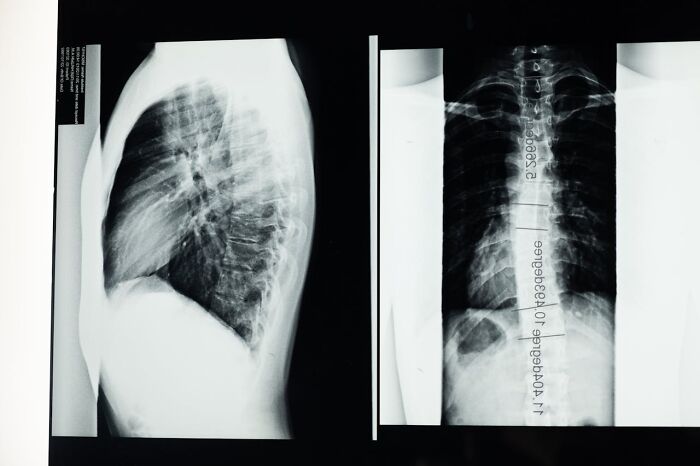

About two weeks later, my mother and I went to his other office and he examined my eye. He asked me if I had experienced any double-vision recently, and I realized I had. So, he explained the possible reasons for the eye (which he diagnosed as sixth cranial nerve palsy): it was an infection, or, in very rare cases, a brain tumor. He ordered a chest x-ray, blood work, and a head MRI.

The blood work and chest x-ray went well and nothing was found. Going into my MRI, my mother was optimistic, but I just had a feeling that the diagnosis was going to be bigger than a little infection. After the MRI, my mother and I got lunch and were high in spirits. When we returned home, I got to work on my classes (they were online- thanks, 2020). A few hours later, my mother ran into my room, very upset, and told me to come to the phone.

My doctor was on the other end. He told me that I had a mass in my brain that was pressing against my sixth cranial nerve. He suggested that it was a very rare form of bone cancer in my brain called chordoma that had grown on my skull base, in the middle of my head. I was diagnosed two days after my nineteenth birthday.

Since then, my diagnosis was confirmed and I had surgery to remove the tumor. I had many complications, like infections and brain fluid leaks, but I made it out. There was about 5–10% of the tumor left, so I underwent proton radiation therapy to kill the rest of the cancer. In a few weeks, I will have been in partial remission for a year :) I also had eye surgery about ten months ago to correct my eye, which was stuck looking inward since my first surgery. Since then, I’ve been dealing with a lot of other issues because of my tumor and treatment, like chronic nerve damage/pain, Hashimoto’s disease and hypothyroidism, but I have a wonderful team of doctors who have provided me with great treatments.